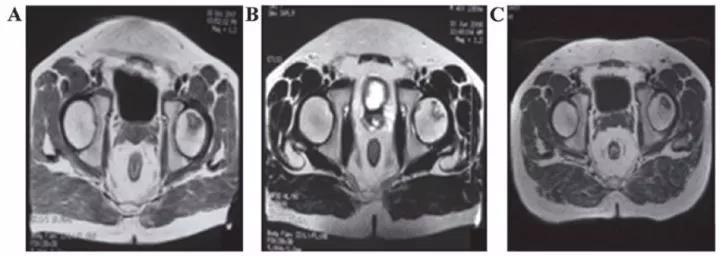

8、泌尿生殖系統疾病

? 不孕不育

子宮內膜受損嚴重,是很多不孕不育女性的噩夢?,F在通過間充質干細胞再生技術修復子宮內膜,可重圓女性的母親夢。

南京鼓樓醫院婦產科胡婭莉教授團隊與中國科學院遺傳與發育生物學研究所戴建武教授團隊聯手,首次在國際上成功研制出膠原支架復合間充質干細胞的方法,結合傳統宮腔鏡技術,實現了受損子宮內膜的功能性修復,幫助3名患者實現做媽媽的夢想。

江蘇鹽城的胡女士在31歲到34歲時,經過三次自然流產,因為流產清宮手術,子宮腔嚴重粘連。南京鼓樓醫院利用間充質干細胞8個月修復了她的子宮內膜,使她成功懷孕,并于2014年7月17日誕下了國內第一位“再生醫學寶寶”。

南京鼓樓醫院的間充質干細胞“子宮內膜再生”術已先后讓13位重度子宮腔粘連致不孕的患者成功受孕并分娩,共計誕生14名健康的“再生醫學寶寶”。